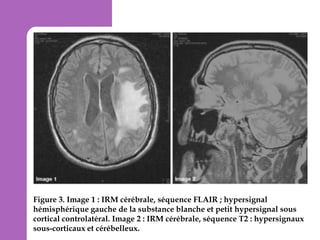

Figure 3. Image 1 : IRM cérébrale, séquence FLAIR ; hypersignal

hémisphérique gauche de la substance blanche et petit hypersignal sous

cortical controlatéral. Image 2 : IRM cérébrale, séquence T2 : hypersignaux

sous-corticaux et cérébelleux.